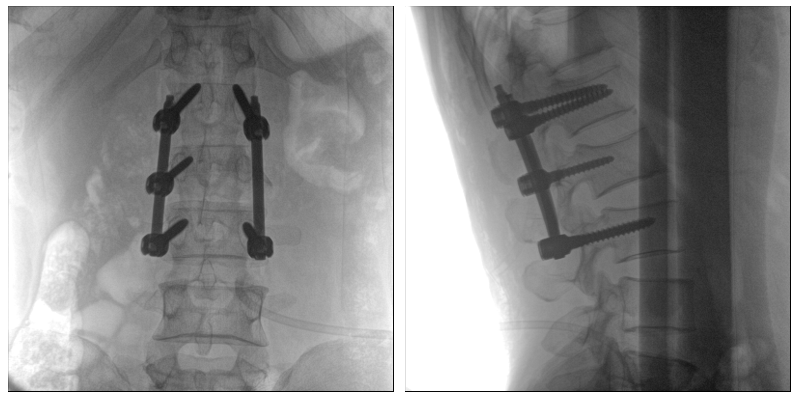

從下圖中可以看到二維影像能夠提供目標區域在某一個平面的重疊影像,雖然因為人體不同組織的密度差異,使得圖像具有較為豐富的信息量,但組織間的相互重疊還是會出現,諸如空間位置等眾多信息在影像中遺失或不可辨認的情況,影響了醫生對信息的收集與應用。

術中二維影像

而三維影像的MPR圖像組可以通過不同平面的切分,使成像區內更豐富的信息得以呈現。尤其是二維影像無法涉及的橫斷面,提供了另一個空間維度的信息量。

術中三維C臂影像